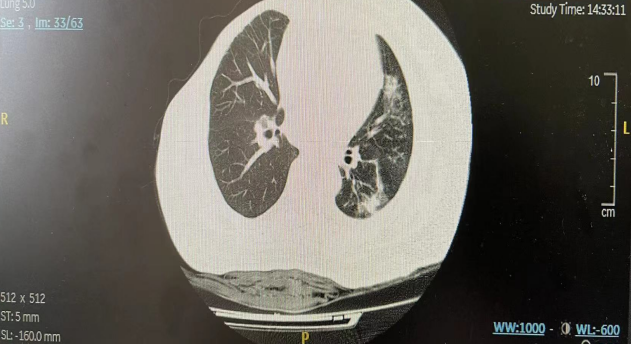

2022年8月起,患者接受戈沙妥珠单抗单药二线治疗,1周期后胸闷气喘明显好转,治疗2周期后(2022年9月)胸部CT:左锁骨区、纵隔多发淋巴结转移,部分较前减小(图4);左侧胸腔积液伴左肺部分膨胀不全较前好转(图5);左肺胸膜下治疗后改变可能同前;胸骨转移同前相仿;右侧锁骨骨质密度局部稍欠均同前相仿。

图4.纵隔淋巴结(左:基线;中:2周期后;最近一次复查)

图5.左侧胸腔积液(左:基线;中:2周期后;最近一次复查)